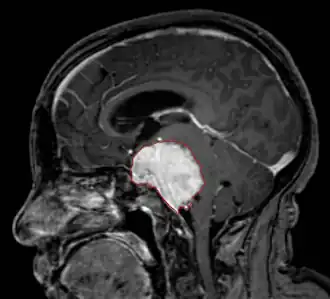

Een hersenoedeem is een zwelling van de hersenen. Dit kan veroorzaakt worden door een zware hersenschudding of door zuurstofgebrek. Dit gaat vaak gepaard met hevige hoofdpijn, shock en bewusteloosheid. De bestrijding van het oedeem geschiedt meestal met bepaalde geneesmiddelen (bijvoorbeeld corticosteroïden) en vaak samen met beademing.